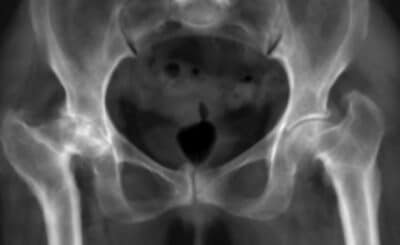

L'articulation de la hanche peut être affectée par diverses pathologies, dont la dysplasie de hanche. Cette affection, q...